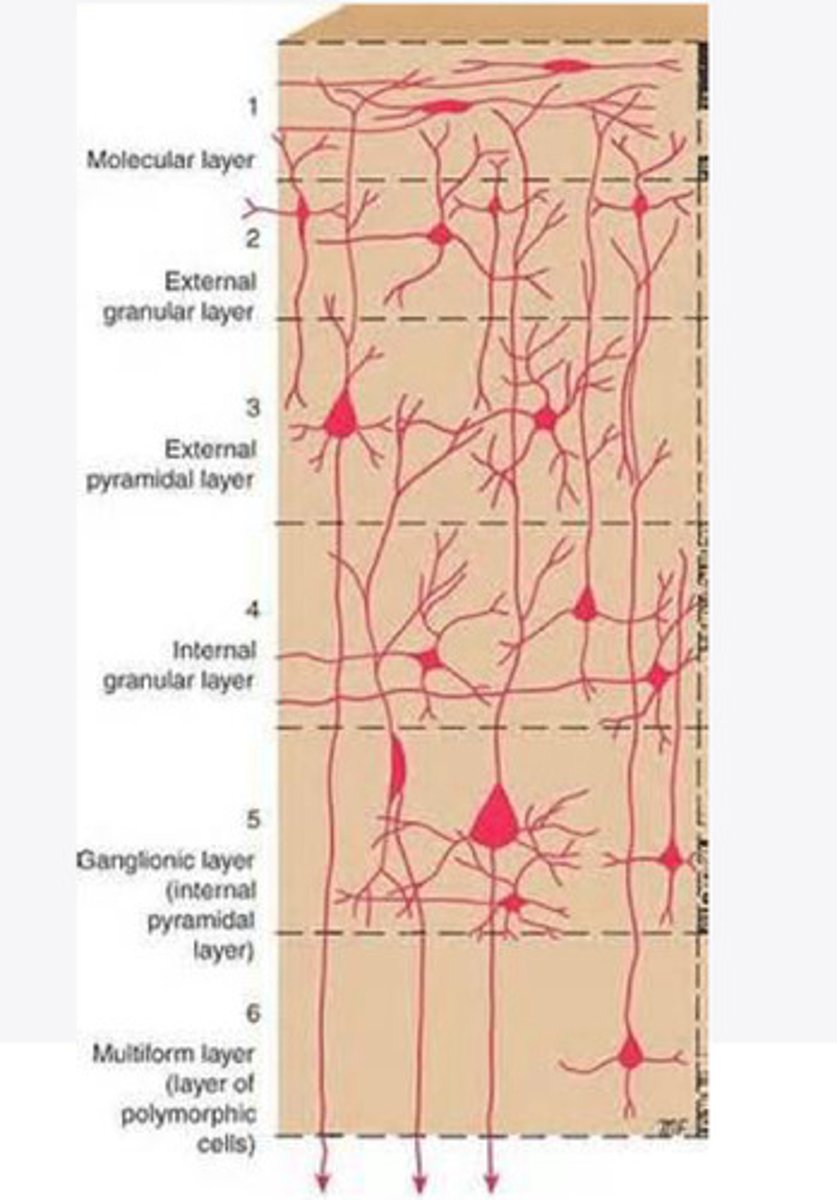

divided into 6 distinct layers, due to varying densities of cell body types within each layer

The cortex of the brain is divided into how many layers? Why is it divided into layers?

Layers of the cortex of the brain pic

2 and 4

What are the layers of the cortex that are associated with input?

3 and 5

What are the layers of the cortex that are associated with output?

molecular layer

What is the name of Layer 1 of the cortex of the brain?

very few cells

Does Layer 1 of the cortex have a lot or few cells?

receives dendrites from internal layers so it may actually function as a coordinating center where layers can communicate action

What does Layer 1 of the cortex do?

1

Every layer sends densities to Layer ____?

1

What layer serves as the "water cooler" of the brain?

external granular layer

What is the name for layer 2 of the cortex of the brain?

receives input from other cortical regions

What is the function of Layer 2 of the Cortex of the brain?

Stellate

What type of cells (stellate/pyramidal) would be most concentrated in Layer 2?

external pyramidal layer

What is the name for layer 3 of the cortex of the brain?

sends output to the other cortical layers

What is the function of Layer 3 of the cortex of the brain?

pyramidal

What type of cells (stellate/pyramidal) would be most concentrated in Layer 3 of the brain?

Layers 2 and 3

What layers are associated with association and commissural fibers?

Layer 3 - axons of cell bodies

Layer 2 - synapse into target areas in Layer 2

What part of the axons is in Layer 2/ in layer 3?

Layer 3 - external pyramidal layer

All axonal cel bodies for association and commissural fibers lie within what layer of the Cortex of the brain?

internal granular

** or called the striate cortex because it is so thick that you can see a line through this layer even in unstrained brain slides

What is the name for the 4th layer of the cortex of the brain?

receives input from the thalamus, geniculocortical layer, and other brainstem areas

What is the function for the 4th layer of the Cortex of the brain?

very thick within the vision, auditory, and somatosensory areas

Is Layer 4 thick or thin within SENSORY areas of the cortex?

Internal pyramidal

What is the name for Layer 5 of the cortex of the brain?

sends axons to the brainstem (corticobulbar) and spinal cord (corticospinal)

What is the function of Layer 5 of the cortex of the brain?

in motor areas of the cortex?

Where is layer 5 very thick in the brain?

the frontal lobe -- very motor heavy

What lobe of the brain will have a thick layer 5 of the cortex of the brain?

the multiform layer

What is the name of layer 6 of the cortex of the brain?

-sends axons back to the thalamus through corticogeniculate fibers

-modulates what information the thalamus sends to the cortex to control the strength of the signal received and modulate what you pay attention to

What is the function of layer 6 of the cortex of the brain?

no

Is layer 6 a motor layer?